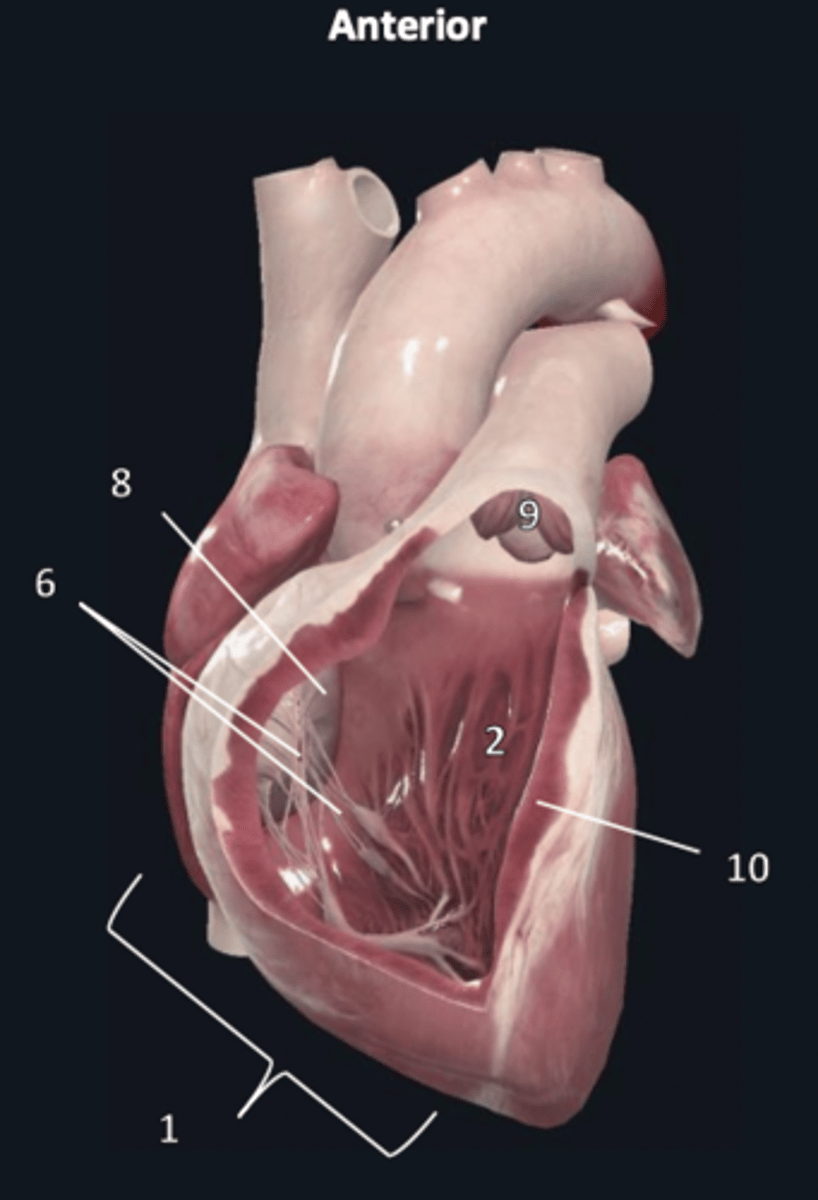

right ventricle

1

trabeculae carneae

2

septal papillary muscle

3

anterior papillary muscle

4

inferior papillary muscle

5

chordae tendineae

6

moderator band

7

tricuspid valve

8

pulmonary semilunar valve

9

interventricular septum

10